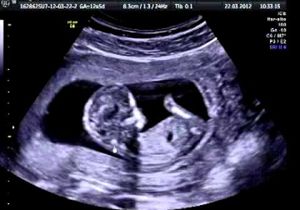

Tra l’altro a quel tempo non c’erano le ecografie e oggi chiunque, a partire dai giovani, possono vedere che dentro quel grembo prima dei tre mesi c’è una vita in carne e ossa: un cuoricino che batte, sangue, cervello, anima. E invece si stravolgono le parole del Papa per portare avanti il proprio sterile totalitarismo libertario che vorrebbe imporre di spegnere la voce di quei medici che si rifiutano di mettere fine a una vita nascente.